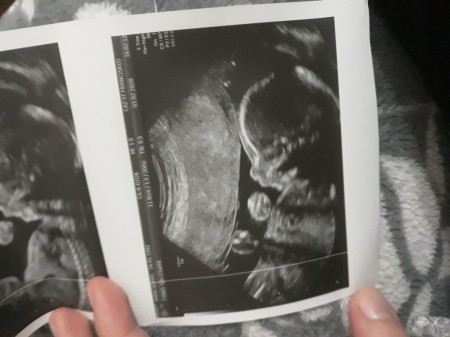

21 Nisan 2020 Hamilelikte Bebek Sağlığı kategorisinde (245 puan) sordu

<3 arkadaşlar özelde başhekim doktorum bana erkek bebek  dedi.

Gebelik haftası 16+5

%99 erkek bebek dedi. Gebelik haftam 16+5

Kemik yapısını bilmem cinsiyetten de anlamam ama bizde 16 haftada öğrendik sizinkinin boyu 18 cm dio bizim 12 idi boyu tabi geriden gelio dedi bi kaç hafta normal dedi ama 18 cm ile 12 cm arasında dağlar kadar fark var bence erkkdir :)

Demi gülüm benim. Ben bu resimden yada resimdeki yazılardan hiç bir şeyi anlamıyorum. Doktorum.har şey yolunda diyor.  Bu arada ilk gebeliğim belki ondan anlamıyorum

Erkek bence de kizlar daha farkli oluyor sanki dur bak resim atayim bak